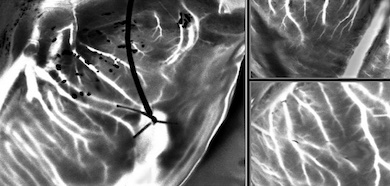

Dynamic speckle reveals details of heart vasculature

The Paris-Saclay project has developed a possible alternative, based on the imaging of dynamic speckle patterns from the beating heart after it has been removed from a donor and kept supplied with blood, an organ preservation procedure termed ex vivo perfusion. The work was published in Journal of Biomedical Optics.

"This optical technique allows high-resolution imaging of the entire peripheral vasculature of the heart in real time," said Elise Colin from Paris-Saclay University.

A sequence of such images enabled vasculatures in the heart as small as 100 microns to be imaged in a few seconds, according to the project team.

If the new technique enables precise visualization of blood circulation, it might in the future prove able to identify myocardial perfusion abnormalities that indicate underlying heart conditions, such as the coronary artery disease of concern for transplantation and for general health.

"The LSOCI method coupled with MPE-SNR allows imaging of the complete peripheral vasculature of a beating heart in a noninvasive way, with high spatial resolution and in only a few seconds," said the project in its paper. "Although clinical transfer will raise many difficulties, it could also be used for the observation of other phenomena in the human arterial system that present periodic excitation of blood flow."